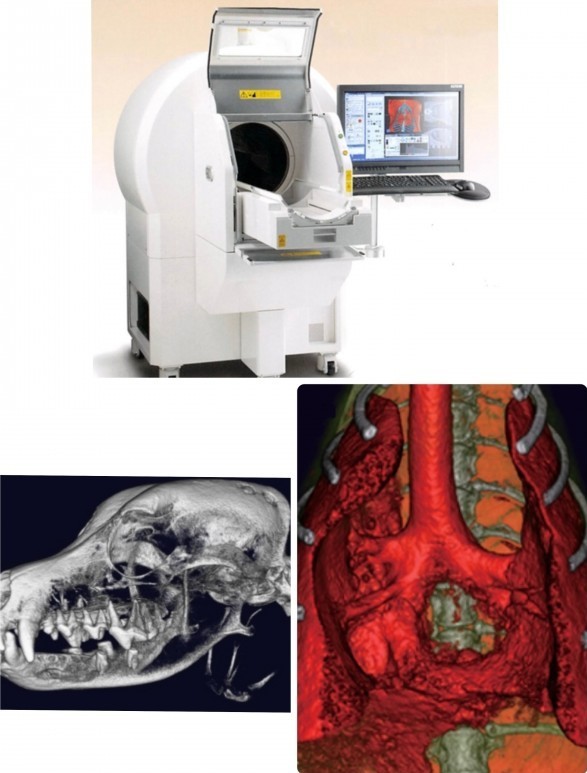

中・小型動物用3DマイクロCT

CTとはコンピューター断層撮影(Computed Tomography)の略で、X線を用いて身体の横断像(輪切り)を撮影することが出来ます。立体3D画像が得られるのも特徴で、主に骨格の異常や臓器系の異常部位、腫瘍性病変の把握に利用されます。

当院では「中・小型動物用3DマイクロCT」を導入しています。エキゾチックペットから猫・小型犬まで撮影可能です。